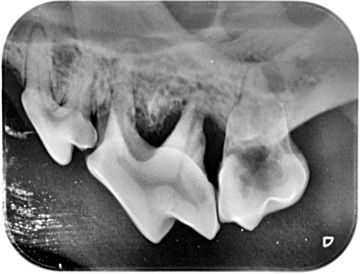

Diagnostics - intraoral X-ray

An X-ray should be taken every time a tooth is missing, discolored or broken. Furthermore, in cases of swollen and inflamed gums, growths in the mouth or even bad breath. Even without these symptoms, it is recommended to take pictures of at least strategic teeth - the teeth of the blockbuster complex and canines - always when removing tartar. Remember that one human year is equal to 5-7 dog years, and humans routinely get dental x-rays at least once every 2 years for a preventative checkup.